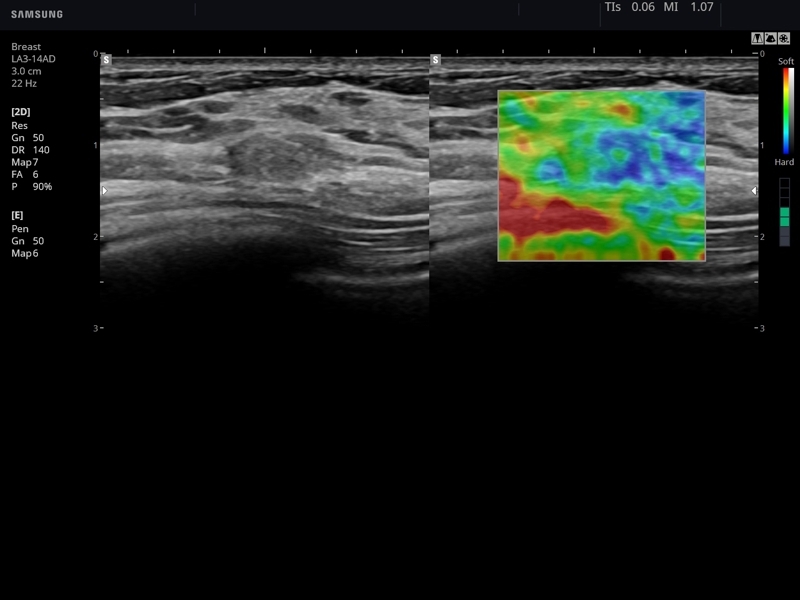

Многие врачи и профессионалы в области здравоохранения высоко оценивают возможности аппарата благодаря его способности к 5D-сканированию и качественной оценке эластичности тканей. Этот сканер оборудован инновационным алгоритмом "машинного обучения", который помогает начинающим специалистам принимать решения, а также автоматически классифицирует образования молочной железы по BI-RADS S-Detect Breast.

• ElastoScan

• E-Strain (эластография, дифференциальная диагностика в онкологии)

• Модуль Elastoscan - программы эластографии (качественная оценка) для исследований щитовидной железы, молочной железы у женщин и предстательной железы у мужчин.

• Mодуль E-Strain - программа количественной оценки эластичности тканей по выбранной зоне (необходим модуль Elastoscan).